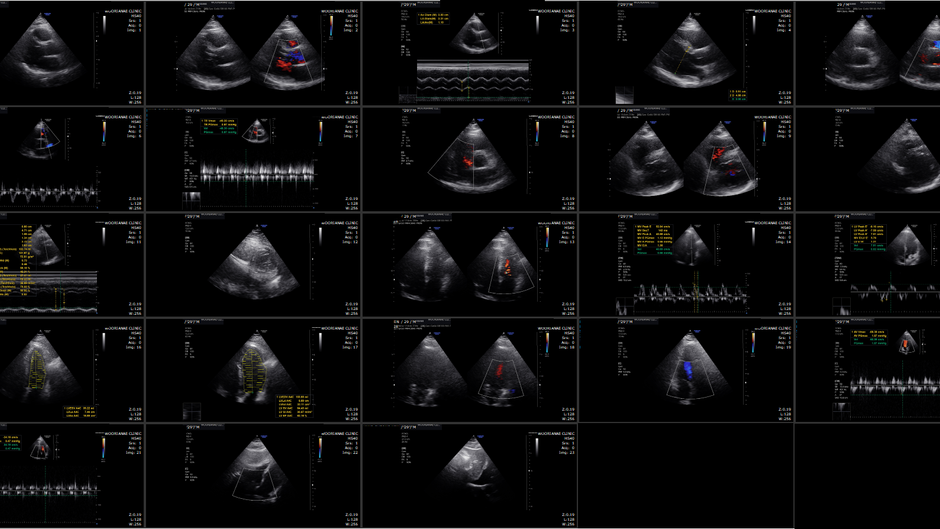

심잡음 평가에서 중등도 대동맥 판막 역류, 경도의 이첨판 협착... 대동맥 확장에 대해 상급병원 진료 - 동대문구 답십리, 장안동, 우리안애 우리안愛 내과

60대 후반 여자 본원에서 혈압약 투약하시는 분으로 과거에 간헐적인 화끈거림으로 갈색새포종 배제위한 24시간 소변검사 시행한적 있음. 이후 혈압약 투약 받던 분으로 이번 방문시 혈압 측정중 불규칙한 맥박이 느껴져 청진을 하니 뚜렷한 (grade...